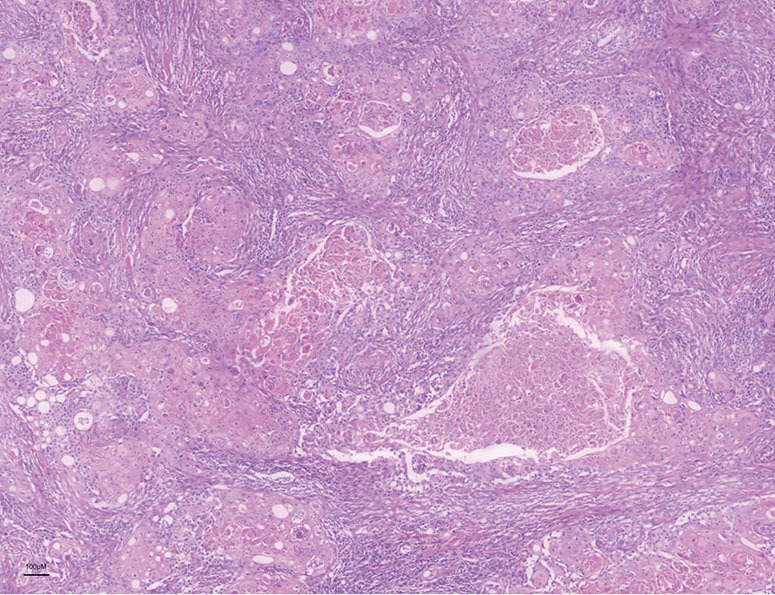

Case description: A 45-year-old female presented with a painless mass in the medial-upper quadrants of right breast and the imaging examination suggested a malignant tumor. She received modified radical mastectomy and axillary sentinel lymph node dissection of the right breast, and the pathological diagnosis was squamous cell carcinoma with HER2 over-expression. Subsequently, she underwent post-operative chemotherapy regimen of doxorubicin, cyclophosphamide, T-docetaxel and trastuzumab (AC-TH) and then received maintenance treatment with trastuzumab and pertuzumab. Clinical follow-up suggests that she had achieved clinical complete remission and has survived for over 4 years.

Conclusions: The diagnosis of PBSCC relies on histomorphology, due to non-specific imaging manifestations. Immunohistochemical (IHC) staining helps to clarify the pathological type, hormone receptor status, HER2 amplification and programmed cell death ligand 1 (PD-L1) expression, which is essential for clinical decision-making. HER2-positive PBSCC patients can benefit from AC-TH chemotherapy and 1-year anti-HER2 therapy is necessary to good prognosis. If possible, dual anti-HER2 therapy combined with trastuzumab and pertuzumab is recommended. Finally, positive clinical prognosis of PBSCC may be attributed to early detection, immediate surgery, precise diagnosis and proper adjuvant treatment strategy.